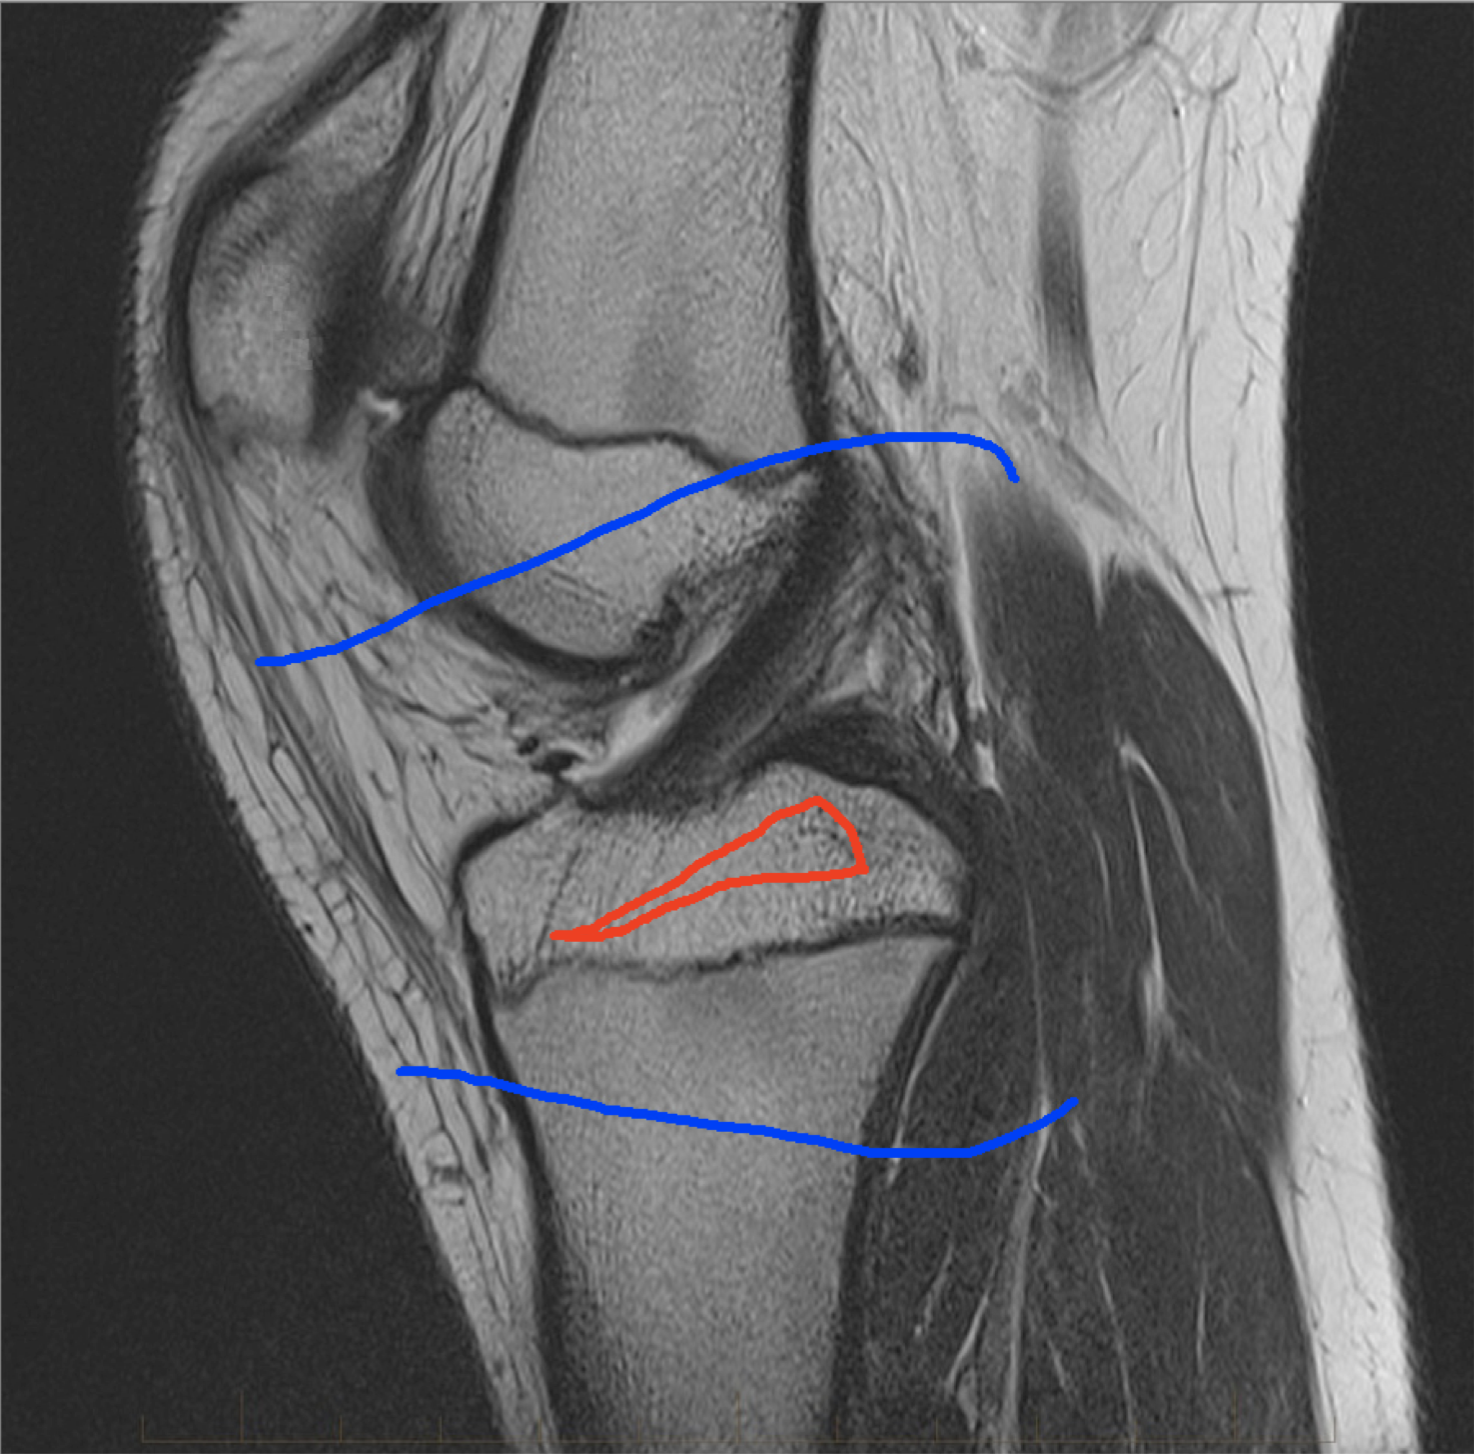

Four sets of test results are shown below. In Test 1 we compare models M1 – M6 to the proposed model M7 for two images which are hard to segment. The first is a CT scan from which we would like to segment the lower portion of the heart, the second is an MRI scan of a knee and we would like to segment the top of the Tibia. See Figure 9 for the test images and the marker sets used in the experiments. In Test 2 we will review the sensitivity of the proposed model to the main parameters. In Test 3 we will give several results achieved by the model using marker and anti-marker sets. In Test 4 we show the initialisation independence and marker independence of the Geodesic Model on real images.

In this test we give the segmentation results for models M1 – M7 for the two challenging test images shown in Figure 9. The marker and anti-marker sets used in the experiments are also shown in this figure. After extensive parameter tuning, the best final segmentation results for each of the models are shown in Figures 10 and 11. For M1 – M4 we obtain incorrect segmentations in both cases. In particular, the results of M2 and M4 are interesting as the former gives poor results for both images, and the latter gives a reasonable result for Test Image 1 and a poor result for Test Image 2. In the case of M2, the regularisation term includes the edge detector and the distance penalty term (see (4)). It is precisely this which permits the poor result in Figures 10(b) and 11(b) as the edge detector is zero along the contour and the fitting terms are satisfied there (both intensity and area constraints) – the distance term is not large enough to counteract the effect of these. In the case of M4, the distance term and edge detector are separated from the regulariser and are used to weight the Chan-Vese fitting terms (see (9)). The poor segmentation in Figure 11(b) is due to the Chan-Vese terms encouraging segmentation of bright objects (in this case), weighting enforces these terms at all edges in the image and near . In experiments, we find that M4 performs well when the object to segment is of approximately the highest or lowest intensity in the image, however when this is not the case, results tend to be poor. We see that, in both cases, models M5 and M6 give much improved results to M2 and M4 (obtained by incorporating the geodesic distance penalty into each). The proposed Geodesic Model M7 gives an accurate segmentation in both cases. It remains to compare M5, M6 and M7. We see that M5 is a non-convex model (and cannot be made convex [39]), therefore results are initialisation dependent. It also requires one more parameter than M6 and M7, and an accurate set to give a reasonable area constraint in (4). These limitations lead us to conclude M6 and M7 are better choices than M5. In the case of M6, it has the same number of parameters as M7 and gives good results. M6 can be viewed as the model M7 with weighted intensity fitting terms (compare (18) and (30)). Experimentally, we find that the same quality of segmentation result can be achieved with both models generally, however M6 is more parameter sensitive than M7. This can be seen in the parameter map in Figure 12 with M7 giving an accurate result for a wider range of parameters than M6. To show the improvement of M7 over previous models, we also give an image in Figure 13 which can be accurately segmented with M7 but the correct result is never achieved with M6 (or M3). Therefore we find that M7 outperforms all other models tested M1 – M6.

(i) (ii) (iii) (iv)

Test 2 – Test of M7’s sensitivity to changes in its main parameters. In this test we demonstrate that the proposed Geodesic Model is robust to changes in the main parameters. The main parameters in (20) are and . In all tests we set , which is simply a rescaling of the other parameters, and we set . In the first example, in Figure 12, we compare the TC value for various and values for segmentation of a bone in a knee scan. We see that the segmentation is very good for a larger range of and values. For the second example, in Figure 13, we show an image and marker set for which the Spencer-Chen model (M3) and modified Liu et al. model M6 cannot achieve the desired segmentation for any parameter range, but which can be attained for the Geodesic Model for a vast range of parameters. The final example, in Table 1, compares the TC values for various values with fixed parameters and . We use the images and ground truth as shown in Figures 12 and 13: on the synthetic circles image we obtain a perfect segmentation for all values of tested, and in the case of the knee segmentation the results are almost identical for any , above which the quality slowly deteriorates.